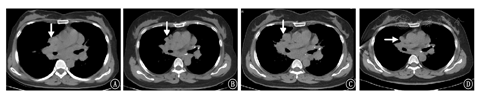

患者女,48岁,2001年在外院行纵隔淋巴结病理检查考虑诊断为"结节病",给予糖皮质激素类药物(泼尼松7.5 mg/d)治疗半年后自行停药,于2012年9月11日开始我院门诊复诊,胸部CT示:双肺门及纵隔淋巴结肿大,考虑结节病;首次发现右上肺气囊(图1A),此后多次复查胸部CT发现肺气囊稍有增加,未行诊治。之后于2016年11月5日患者无明显诱因出现自发性气胸至我院门诊行胸部CT示:右侧气胸,肺压缩约50%;双肺多发肺囊肿,双肺门淋巴结肿大(图2A),双肺弥漫分布为主(图1B),行胸腔闭式引流后复查胸部CT可见右侧气胸基本吸收。出院后又多次来我院门诊复诊查胸部CT仍可见双肺弥漫性肺气囊且数目逐渐增多,肺门淋巴结肿大较前略有缩小,遂调整为口服泼尼松(2.5 mg/d)维持,肺部气囊仍未行诊治。直至2019年5月11日至我院门诊复诊行泌尿系平扫CT又发现左肾乏脂肪错构瘤及右肾错构瘤(图1C),免疫病理:Melan-A(+),HMB-45(散在+),SMA(+),S-100(+),CD34(血管+),Desmin(局灶+),Ki-67(LI约10%+),H-Caldesmon(+),PCK[AE1/AE3](-)。综合考虑诊断为"右肾血管平滑肌瘤",给予抗感染、解痉及对症治疗,术后恢复可。术后规律复诊行胸部CT示:双侧肺气肿或肺气囊逐渐增多(图1D),考虑淋巴管平滑肌瘤病(lymphangiomyomatosis,LAM)可能,肺门淋巴结肿大较前明显缩小(图2B)。为求进一步明确诊断患者于2019年12月前往北京协和医院就诊,双肺CT示:双肺弥漫多发囊性病变,符合淋巴管平滑肌瘤;双肺门和纵隔淋巴结肿大,符合结节病表现;行68CA-NEB PET-CT符合肺淋巴管肌瘤病表现,行肺功能检查提示中度阻塞性通气功能障碍(FEV1/FVC 69.59%)弥散功能降低(DLCO SB 68.5%,DLCOCSB 68.5%),舒张试验阴性;ACE 21 U/L;VEGF-D 542 ng/L。综合考虑为"淋巴管平滑肌瘤病结节病",北京协和医院给予口服泼尼松2.5 mg(1次/d)、西罗莫司2 mg(1次/d)等治疗后稍好转,服用西罗莫司2个月后自行停用,继续口服泼尼松2.5 mg/d维持。于2020年5月6日患者因逐渐出现"气喘"和"呼吸困难"收入我院呼吸内科。查体:意识清楚、精神欠佳,双肺呼吸粗,双肺未闻及干湿性啰音。既往无吸烟,否认家族遗传病史。

入院诊断:淋巴管平滑肌病结节病。诊疗经过:入院后实验室检查:白细胞为4.99×109/L,中性粒细胞百分比79.2%,淋巴细胞百分比5.6%,可溶性抗原(ENA):抗核抗体(ANA-IgG)阳性,其他实验室检查结果均显示阴性。胸部三维成像CT仍可见双侧肺气囊,大小不一(图1E),双肺多发斑片影、双肺门淋巴结较以往增多、增大,考虑结节病进展?(图2C),支气管镜及病原学检测均未见异常。予以波尼松30 mg,1次/d口服治疗3周,每3周减少10 mg,直至维持量10 mg,1次/d,继续服用西罗莫司2 mg,1次/d治疗。治疗7天后复查肺功能:中度阻塞性通气功能障碍(FEV1/FVC为62%,FEV1%pred为82%,轻度弥散功能下降DLCO%pred为75%,DLCO/VA为91%)较之前外院复查肺功能稍有恶化。遗憾的是患者拒绝行肺气囊活检。2020年6月16日开始来我院门诊复诊,胸部CT示:双肺斑片状实变灶较前减少,肺部感染病灶较前大部分吸收(图1F)。肺门淋巴结肿大较前缩小(图2D),气喘症状改善。